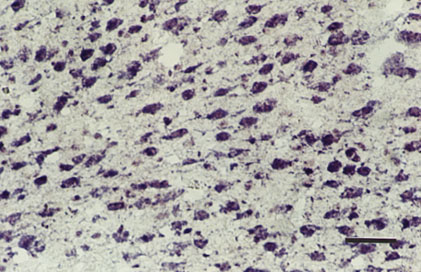

Figure 2. NMDAR1 probe expression in normal cat layer IV

Light micrograph of layer IV in the right visual cortex of normal cat showing positive expression of the nRNA NMDAR1 probe. The bar represents 100 mm.